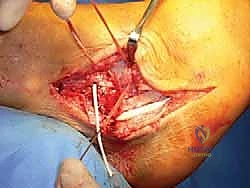

الخطوة 3: الوصول إلى المفصل وإزالة الأنسجة التالفة

يتم عمل شق جراحي مقوس على الجزء الخارجي من الكاحل. يقوم الجراح بكشف العظام (الشظية، الكاحل، الكعب) وإزالة بقايا الأربطة الممزقة والمتهالكة، وتنظيف المفصل من أي نتوءات عظمية أو التهابات مزمنة.

الخطوة 4: حفر الأنفاق العظمية (Bone Tunnels)

هذه هي المرحلة الأكثر دقة. باستخدام أدوات حفر دقيقة (Drill Guides) موجهة بالأشعة داخل غرفة العمليات، يقوم الدكتور هطيف بحفر أنفاق صغيرة جداً في المواقع التشريحية الدقيقة لمرتكزات الأربطة الأصلية:

* نفق في عظمة الشظية (Fibula).

* نفق في عظمة الكاحل (Talus) لتعويض رباط ATFL.

* نفق في عظمة الكعب (Calcaneus) لتعويض رباط CFL.